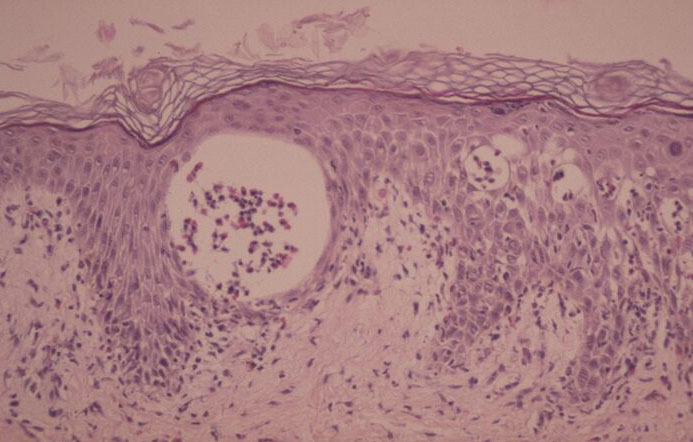

The vesicles seen during the first stage arise within the epidermis and are associated with spongiosis. They are of the type seen in dermatitis . However, they differ from the vesicles of dermatitis by the numerous eosinophils within them and around them in the epidermis (eosinophilic spongiosis) . The epidermis between the vesicles often shows single dyskeratotic cells and whorls of squamous cells with central keratinization. Like the epidermis, the dermis shows an infiltrate containing many eosinophils and some mononuclear cells.

The alterations in the second stage consist of acanthosis, irregular papillomatosis, and hyperkeratosis. Intraepidermal keratinization, consisting of whorls of keratinocytes and of scattered dyskeratotic cells, is often more pronounced than in the first stage. The basal cells show vacuolization and a decrease in their melanin content. The dermis shows a mild, chronic inflammatory infiltrate intermingled with melano-phages. This infiltrate extends into the epidermis in many places.